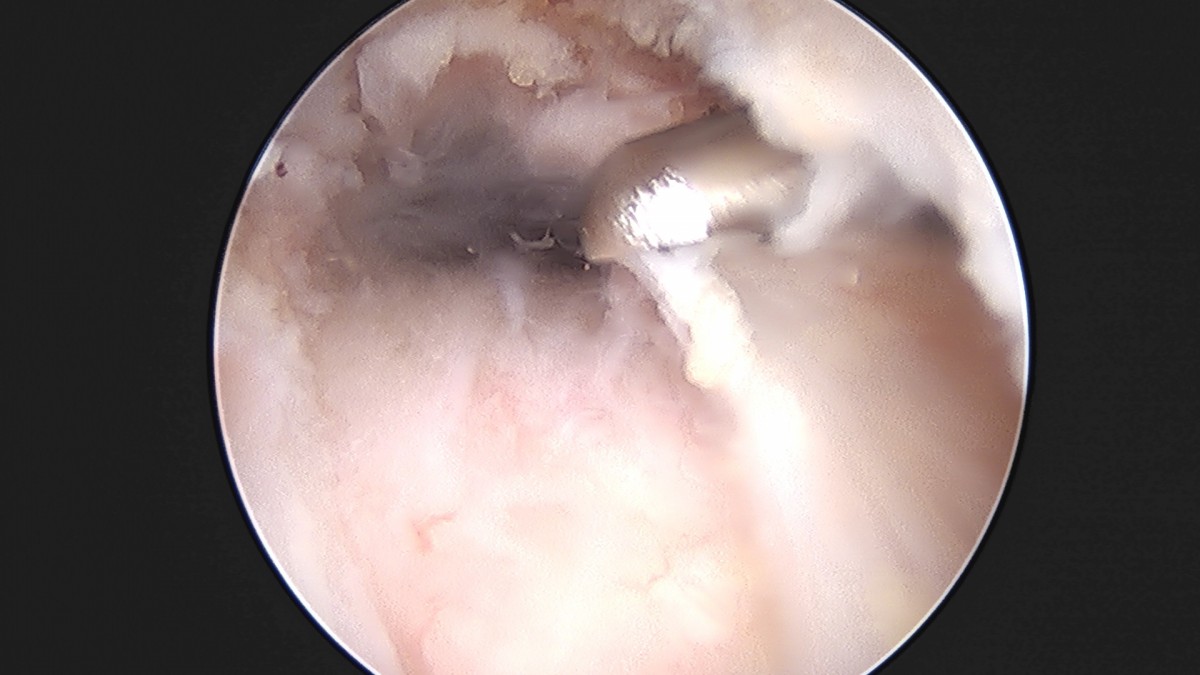

이재상원장님 어깨 견봉하 감압술 이승O 환자

작성자 최고관리자 댓글 0건 조회 806회 작성일 25-09-16 15:26